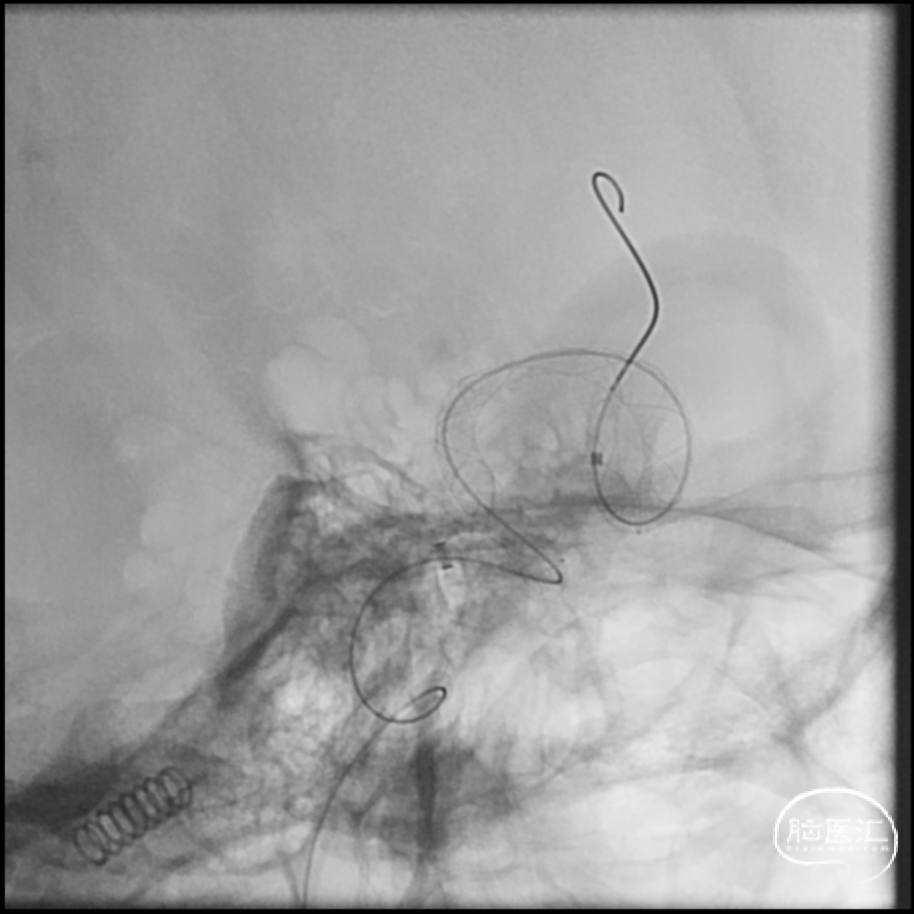

回撤微导管造影

L ICA

Pre-OP

Post-OP